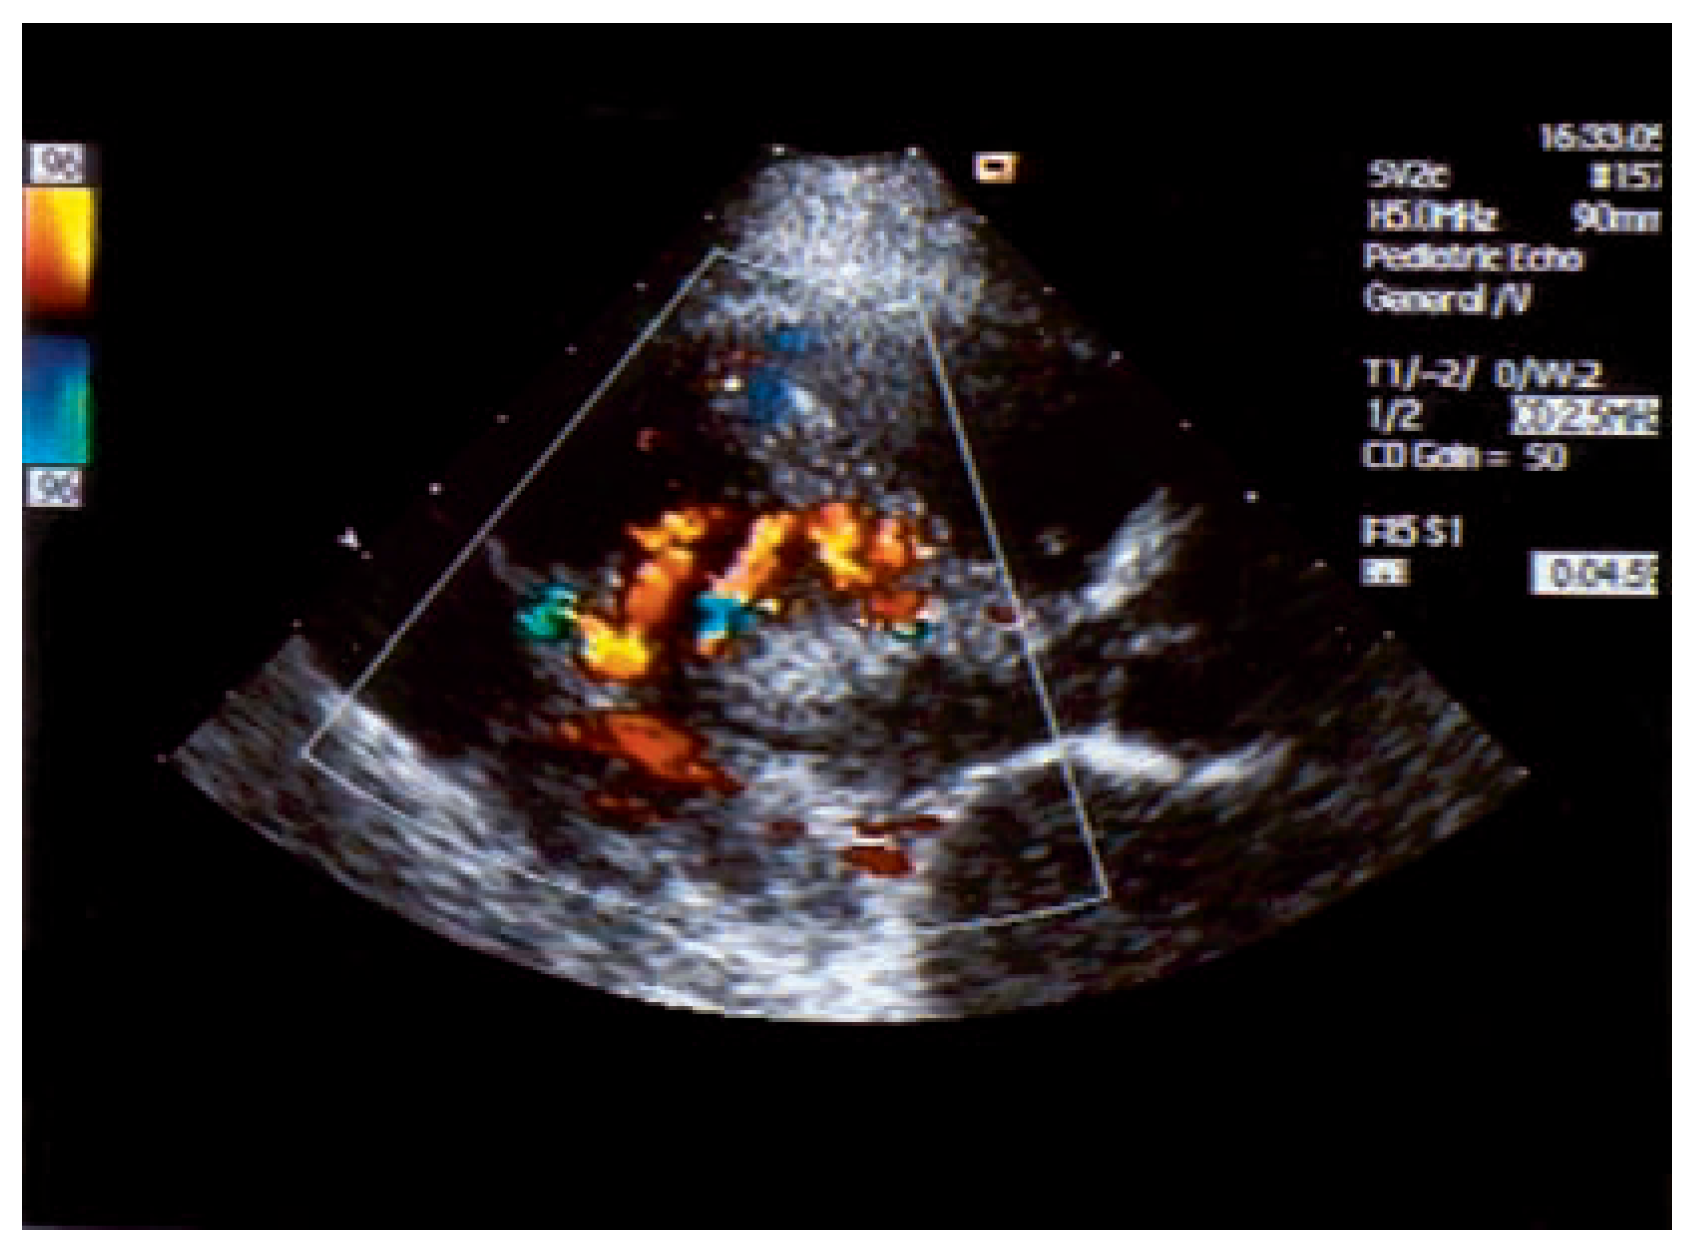

Asymptomatic Bland-White-Garland Syndrome in a 13-Year-Old Girl

Case report